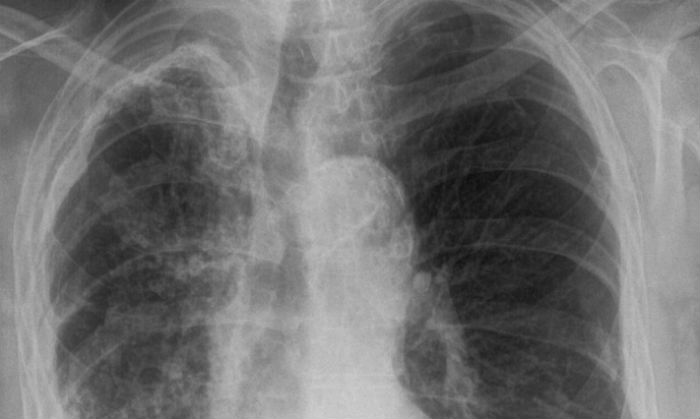

Cine a fost Marius Nasta. Istoria neștiută a primului spital de tuberculoză din București

Alertă la o școală din Galați: O profesoară a fost diagnosticată cu tuberculoză